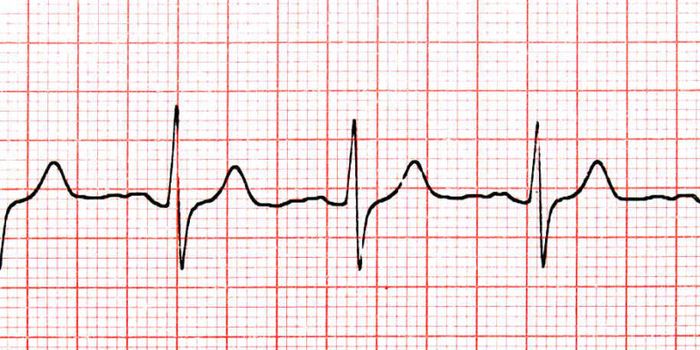

Read the latest articles about newly released neuroscience research and advances in experimental techniques. Topics include research news in neuroscience, neurology, psychology, brain science and cognitive sciences.